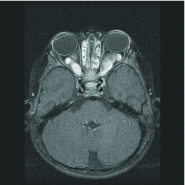

Figure 1.

Figure 1.. Unilateral optic nerve glioma in a 2-year-old child without neurofibromatosis type 1.